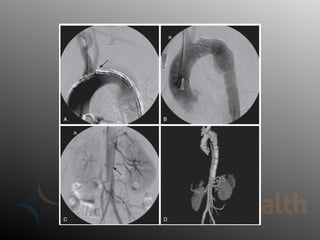

Surgical Repair – Type B

• Endovascular repair was initially

used for complicated type B

dissections with malperfusion or

(impending) rupture

– promotion of aortic remodeling has

promise for all patients with type B

dissections

• Goals of TEVAR

– Cover proximal entry tear

– Obliterate false lumen 

thrombosis

– Restore flow to visceral vessels

• Fenestrated grafts allow for selected

angioplasty/stenting of involved branch vessels

– Promotes false lumen obliteration and reverses

malperfusion

– Technically challenging, not available everywhere

Surgical Repair –Type B • Endovascular repair was initially used for complicated type B dissections with malperfusion or (impending) rupture – promotion of aortic remodeling has promise for all patients with type B dissections • Goals of TEVAR – Cover proximal entry tear – Obliterate false lumen  thrombosis – Restore flow to visceral vessels

Surgical Repair –Type B • Fenestrated grafts allow for selected angioplasty/stenting of involved branch vessels – Promotes false lumen obliteration and reverses malperfusion – Technically challenging, not available everywhere

• #26 A) Complex aortic aneurysm extending between aortic arch and thoracic aorta region, (B) Open surgical repair, (C) Endovascular repair, (D) Frozen elephant trunk hybrid repair. BA—Brachiocephalic artery, LCCA—Left common carotid artery, LSA—Left subclavian artery.

• #31 Angiography pictures of TEVAR